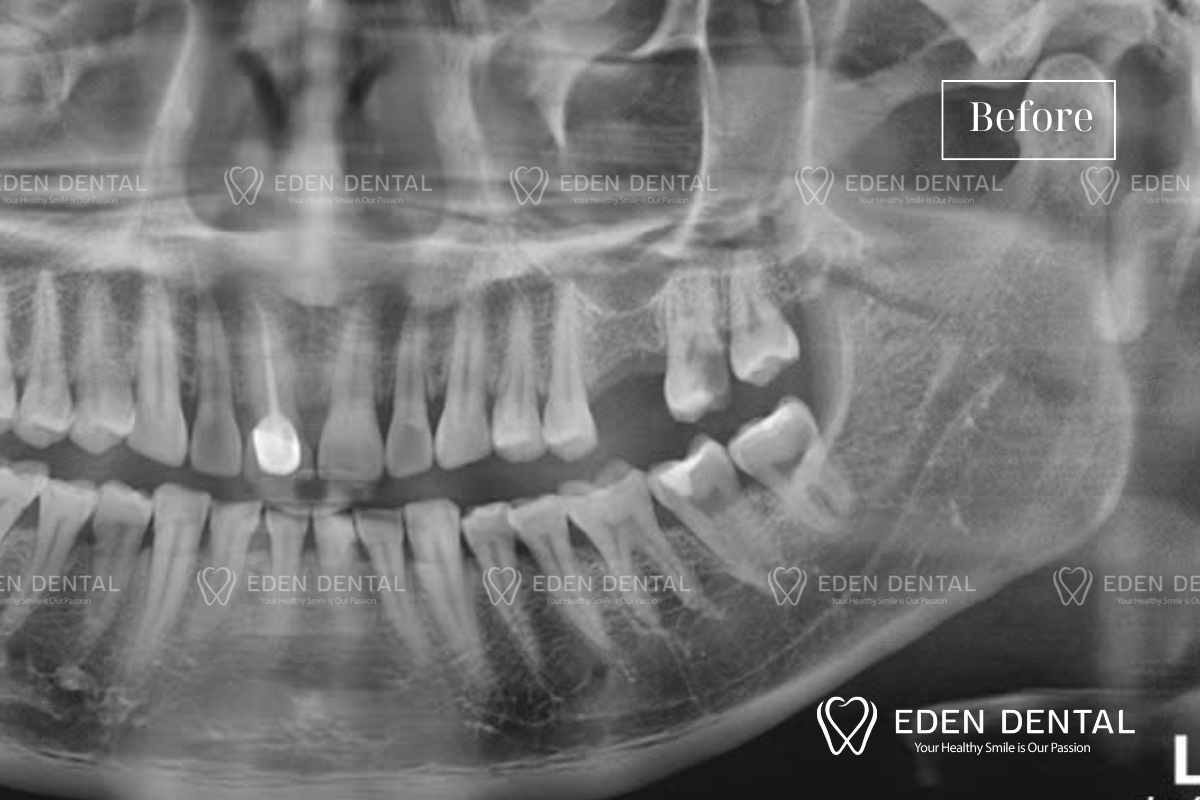

Tình trạng ban đầu – Mất răng 26, viêm tủy răng 27

- Mất răng 25 phân hàm 2 bên trái hàm trên, khách hàng mất tự tin khi cười lớn thấy khe hở

- Răng 26 sâu phía xa đã tới tủy gây đau nhức khi ăn uống